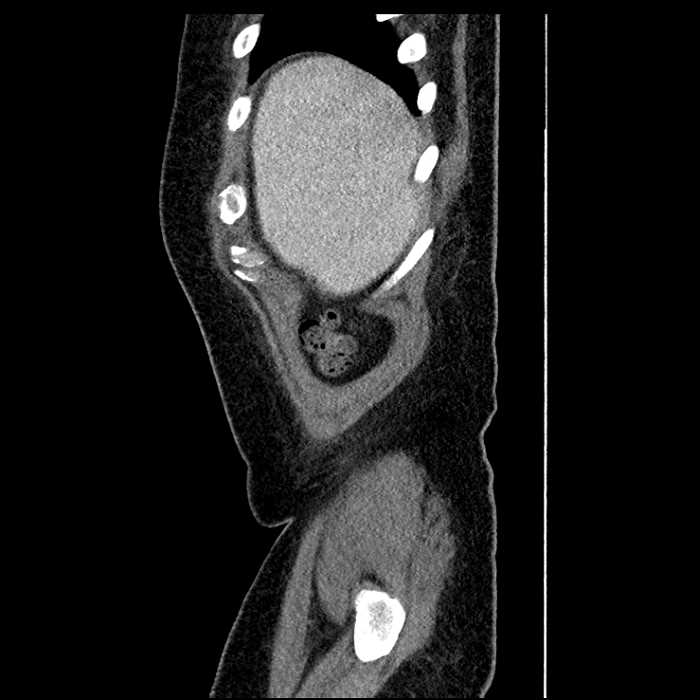

• Large fluid density structure in hepatic segments 7 and 8 measuring 10 x 7 x 7 cm with internal septation and circumferential ill-defined low density compatible with edema

• Peripherally enhancing subcapsular collections along the anterior margin of the left hepatic lobe measuring 3 x 1 cm and 2 x 1 cm

Acute sigmoid diverticulitis complicated by a small contained perforation and a large abscess in the right hepatic lobe. Additional small subcapsular abscesses along the anterior margin of the left hepatic lobe.

Additionally, loss of the normal fat plane between the peridiverticular collection and adjacent thickened loops of small bowel raises the potential for an enterocolonic fistula.

• The classic CT imaging appearance is a double target sign with internal low density surrounded by an internal enhancing rim (capsule) and a low density external rim (edema)

Hepatic abscess showing the double target sign with low density internally surrounded by a thin inner enhancing rim (red arrow) and ill-defined outer low density rim (yellow arrow). Blue arrow indicates an internal septation. Red arrows: additional smaller subcapsular abscesses. Red arrow: focal contained perforation associated with diverticulitis.